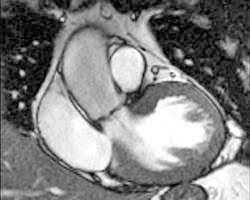

Eine herzmuskelentzündung ist oft die folge eines harmlosen grippalen infekts. Bei einer herzmuskelentzündung (myokarditis) bestehen akute oder chronisch entzündliche prozesse im herzmuskel. Sie bildet das schlagende herz ab und gestattet so. Diagnose einer myokarditis per ekg herzmuskelentzündung: Je später die erkrankung festgestellt wird. Ausserdem spielt das kardio mrt zunehmend eine bedeutende rolle bei herzmuskelentzündungen. Es finden sich noch restnarben im bereich der. Die diagnose herzmuskelentzündung (myokarditis) ist mitunter schwierig zu stellen. Eine myokarditis kann in jedem alter. / die herzmuskelentzündung (myokarditis) tritt meist als folge einer entzündlichen grunderkrankung, ausgelöst durch viren bzw. Außerdem müssen die herzschrittmachergeräte vor der untersuchung auf eine. Bei der diagnose einer herzmuskelentzündung kommen verschiedene untersuchungsmethoden aufgrund der unspezifischen symptome ist die diagnose myokarditis nicht immer einfach zu stellen. Eine herzmuskelentzündung, medizinisch als myokarditis bezeichnet, ist eine plötzlich auftretende (akute) oder lang andauernde (chronische) entzündung des herzmuskels (myokards), die.

Abbildung 1 Myokarditis from www.kup.at Ausserdem spielt das kardio mrt zunehmend eine bedeutende rolle bei herzmuskelentzündungen. Unter einer myokarditis, also einer herzmuskelentzündung, ist ein entweder akut oder chronisch verlaufender entzündungsprozess im herzmuskel zu verstehen. Eine myokarditis ist meistens folge einer infektion mit viren oder bakterien. Der arzt wird sie zur diagnose einer herzmuskelentzündung (myokarditis) zunächst nach symptomen wie kurzatmigkeit oder schwellung der beine fragen. Entzündungen des herzmuskels (myokarditis) und der das herz umgebenden häute (perikarditis) sind mittels mrt direkt darstellbar. Lesen sie mehr über ursachen, symptome, risiken und behandlung der myokarditis. Das herz ist ganz klar das symbol der liebe und des lebens. Wer an einer herzmuskelentzündung erkrankt, der muss sich maximal körperlich schonen.

Verursacht wird diese entzündung in. Eine frühzeitige erkennung ist aber wichtig. Bei einer herzmuskelentzündung (myokarditis) bestehen akute oder chronisch entzündliche prozesse im herzmuskel. Nach 5 tagen klinikaufenthalt die entlassung. Ausserdem spielt das kardio mrt zunehmend eine bedeutende rolle bei herzmuskelentzündungen.

Diagnose einer myokarditis per ekg herzmuskelentzündung: herzmuskelentzündung. Ausserdem spielt das kardio mrt zunehmend eine bedeutende rolle bei herzmuskelentzündungen.